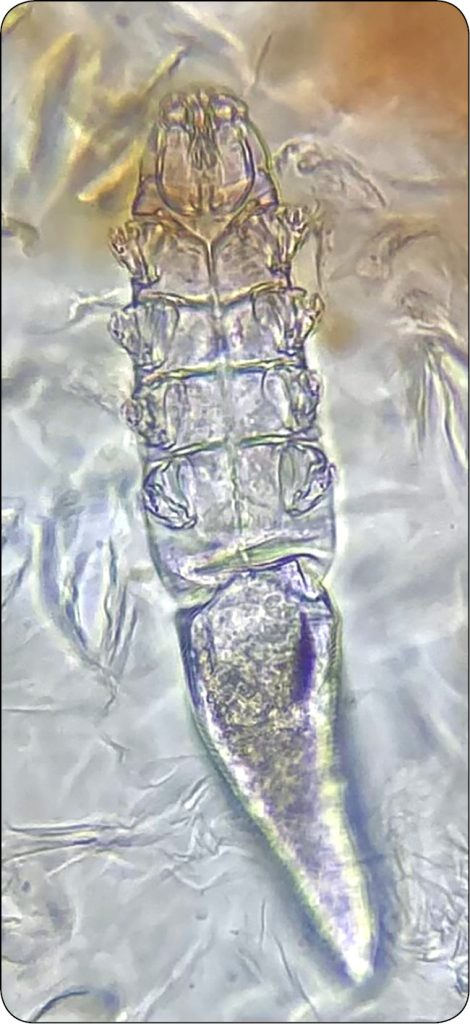

U psów stwierdzany jest najczęściej Demodex canis (ryc. 1a-b).